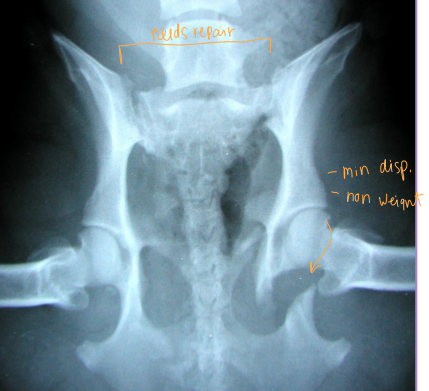

Pelvis Fractures

Considerations: Multi physes, normally breaks at multi sites

Sciatic n.: through ischiatic notch

Weight transfer: paw → tibia → femur → acetabulum → ilium → SI joint

Et: males > females, trama

Dt: Rads, CT for complex fractures/Sx planning

Tx:

Rx: non-displaced, unilateral, non-articular, non-weight-bearing fractures

6 w crate rest, sling, pain control, controlled walks, PT

Sx: ilium/acetabulum/SI joint (weight-bearing), bilateral fractures, displacement, colon compromise, pelvic canal compromise (parturition), sciatic entrapment

Ilium: plate + screws

Acetabulum: plate + screws, cross pins, PMMA

SI joint: screw stabilization